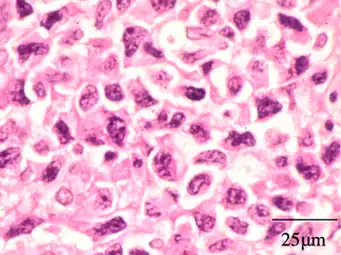

Histology

On histologic examination, nasal polyps consist of hyperplastic edematous (excess fluid) connective tissue with some seromucous glands and cells representing inflammation (mostly neutrophils and eosinophils). Polyps have virtually no neurons. Therefore, the tissue that makes up the polyp does not have any tissue sensation and the polyp itself will not be painful.[6] In early stages, the surface of the nasal polyp is covered by normal respiratory epithelium, but later it undergoes metaplastic change to squamous type epithelium with the constant irritation and inflammation. The submucosa shows large intercellular spaces filled with serous fluid.[15]

Benign mixed inflammation of an inflammatory nasal polyp.

Extranodal NK/T cell lymphoma, nasal type for comparison.[16] These lymphoma cells are typically monotonous, with folded nuclei, indistinct nucleoli and moderate amount of cytoplasm.[17]